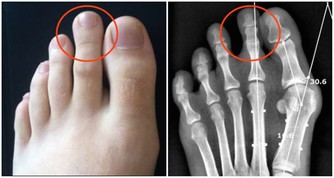

腳這個地方變黑,你就要小心了!!可能是癌症前兆…一定要注意了!!千萬不要忽視。。。。。。 小編就帶你一下你不知道的那些腳部信號的暗示以及一些需要注意的養生常識。看看以下哪些情況是你有過的吧。 1、足部的黑點 我們總是把皮膚癌和日曬聯繫起來,所以我們通常不會檢查腳上的黑點。然而,作為皮膚癌中最危險的黑素瘤,就可能發展到不經常接觸陽光的部位。黑素瘤甚至可能出現在腳指甲下面,看起來像是個黑點兒。 2、腳趾有「黑痣」 我們經常會在身體各個部位看到大小不同,甚至凹凸不平的黑點,這些黑點我們稱之為「黑痣」。腳趾上更是容易看到這些黑痣。那麼黑痣和癌症又有哪些聯繫呢?黑痣本身是天然無公害的,但是黑痣一旦惡化,演變成皮膚癌變將會危及我們的生命安全,即我們經常所說的癌變。 腳趾上的黑痣由於其特殊的位置就很有可能演變成為黑色素瘤。

惡性黑色素瘤是皮膚癌的一種,雖然在中國還不是很常見,但是在歐美地區卻是常見的惡性腫瘤之一。在我國不常見並不意味著黑痣對人體是無害的,近幾年來皮膚癌在我國的發病率也逐漸升高,所以我們還是需要了解其產生的原因,事先做好防護措施,防患於未然。 為什麼說腳趾上的黑痣更容易演變成癌症因子呢?因為黑痣在正常情況下癌變的機率是比較小的,但是如果經常遇到摩擦、擠壓,將會增大其癌變的可能性。我們的腳趾常年處於摩擦和擠壓的狀態下,所以更加容易造成癌變。 黑痣本身就是我們身體與生俱來的良性腫瘤。後天由於生活環境的影響以及自身各個器官的病變,導致了其進一步惡化為黑色素瘤。 還有一部分認為,黑痣只有在暴曬的情況下才會演變成黑色素瘤,但是我們正常情況下是不會暴曬到腳趾部位的。所以我們會容易忽略掉腳趾上的「癌症病毒」。但是,作為皮膚癌中最危險的黑色素瘤,是非常容易發展到不經常接觸陽光的部位。黑素瘤甚至可能出現在腳趾甲下面,看起來就像是一個普通的黑點。 所以如果腳趾部位出現黑痣的話,請大家要做好保護措施,經常觀察黑痣是否有異常變化,如果出現異常請儘快就醫。 3、勺子狀的腳指甲 有時對指甲的傷害或是長期接觸石油基質溶劑可能造成凹陷的像勺子一樣的腳趾形狀。同時,缺鐵也可能會形成這種特殊形狀。